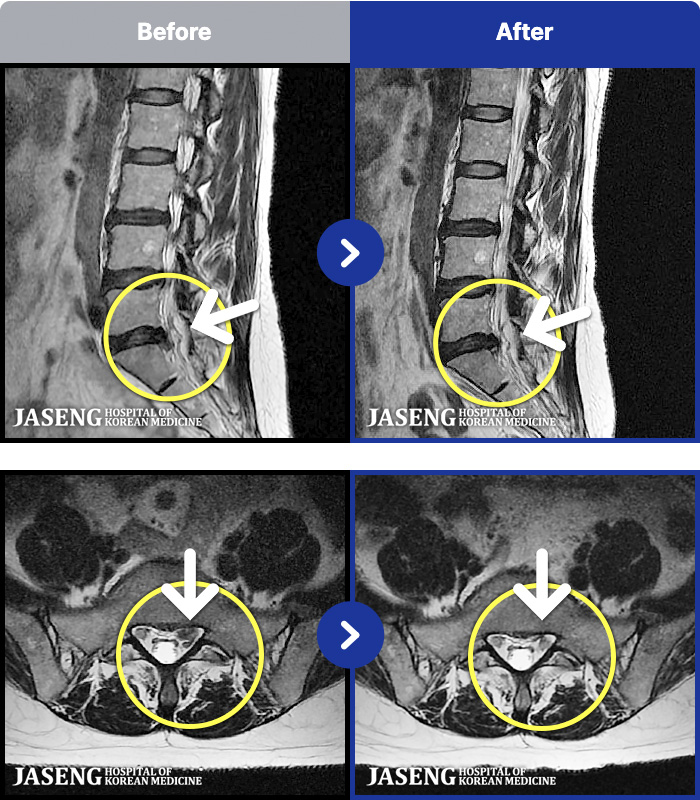

1,268 MRI ũ ʸ Ȯϼ.